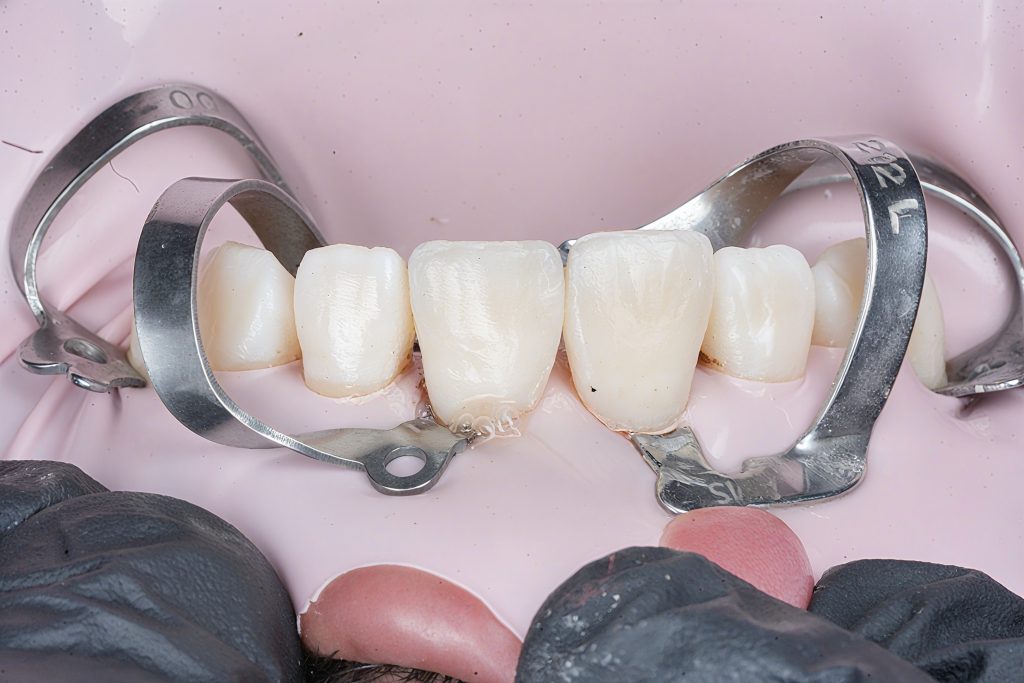

5. Layering Strategy (Bio-Emulation)

Palatal Shell

- A clear matrix was positioned to mimic the natural incisal curvature.

- A translucent enamel shade was placed to form the palatal wall.

Mamelon Build-Up

- A body shade (Clearfil Majesty Body) was sculpted in mamelon patterns.

- Depth effect enhanced with grey/ochre stains.

Halo & Incisal Translucency

- A white tint was used to create a natural incisal halo band.

- Layered translucent enamel shade to cover stains subtly.

Facial Layering

- Thin enamel layers were added to control value, avoiding excessive opacity.